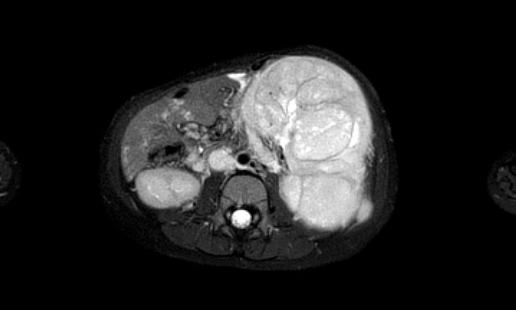

Hình ảnh MRI của một bé gái chín tháng tuổi có khối u ở bụng trái. MRI cho thấy khối u tuyến thượng thận trái, một phần đặc, một phần nang. Có nhiều di căn gan.

Khối u đã được sinh thiết. Có tình trạng chảy máu liên tục qua kim dẫn đường. Vào cuối thủ thuật, hai nút bọt gelatin đã được đặt vào (các dải tăng âm (mũi tên)).